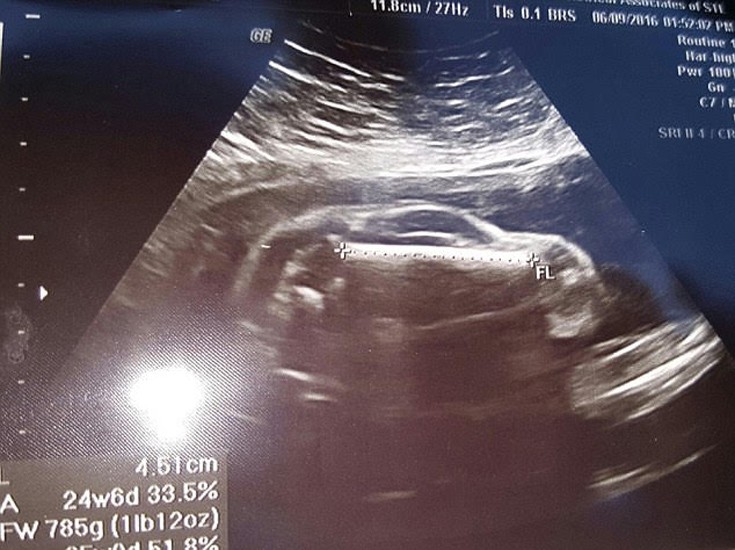

Ο μελλοντικός πατέρας προκάλεσε γέλιο αλλά και δυσπιστία με τη φωτογραφία του υπερηχογραφήματος της εγκύου γυναίκας του το οποίο μοιάζει να δείχνει ένα μικρό όχημα αντί για μωρό.

Η φωτογραφία που ανέβηκε στο Reddit από τον ίδιο με σχόλιο: «Η γυναίκα μου είναι έγκυος σε ένα σπορ αυτοκίνητο» συγκέντρωσε πάνω από 450 σχόλια κυρίως χιουμοριστικά με τον ίδιο να παραδέχεται ότι απλώς έτυχε να φαίνεται έτσι και ότι η εικόνα δεν έχει υποστεί καμία επεξεργασία.